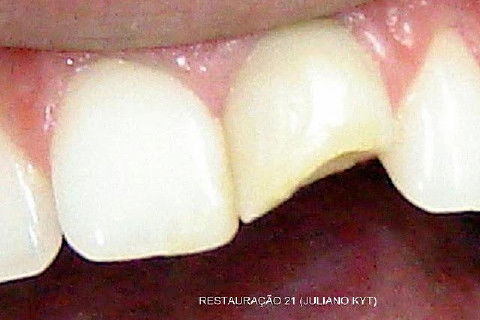

Bom, aí procurou o colega Dr. Juliano Kyt, que gentilmente salvou o que restou...

Nos falamos por telefone e eu lhe expliquei o histórico todo do dente, enviei-lhe o CC por e-mail e lhe pedi que fizesse um trabalho conservador, que oportunamente eu faria uma faceta ou CT em porcelana.

O que está escrito ao lado das fotos são palavras do colega Dr. Juliano Kyt. Ele autorizou-me postar as fotos aqui, inclusive convidei-o para participar do iDent.